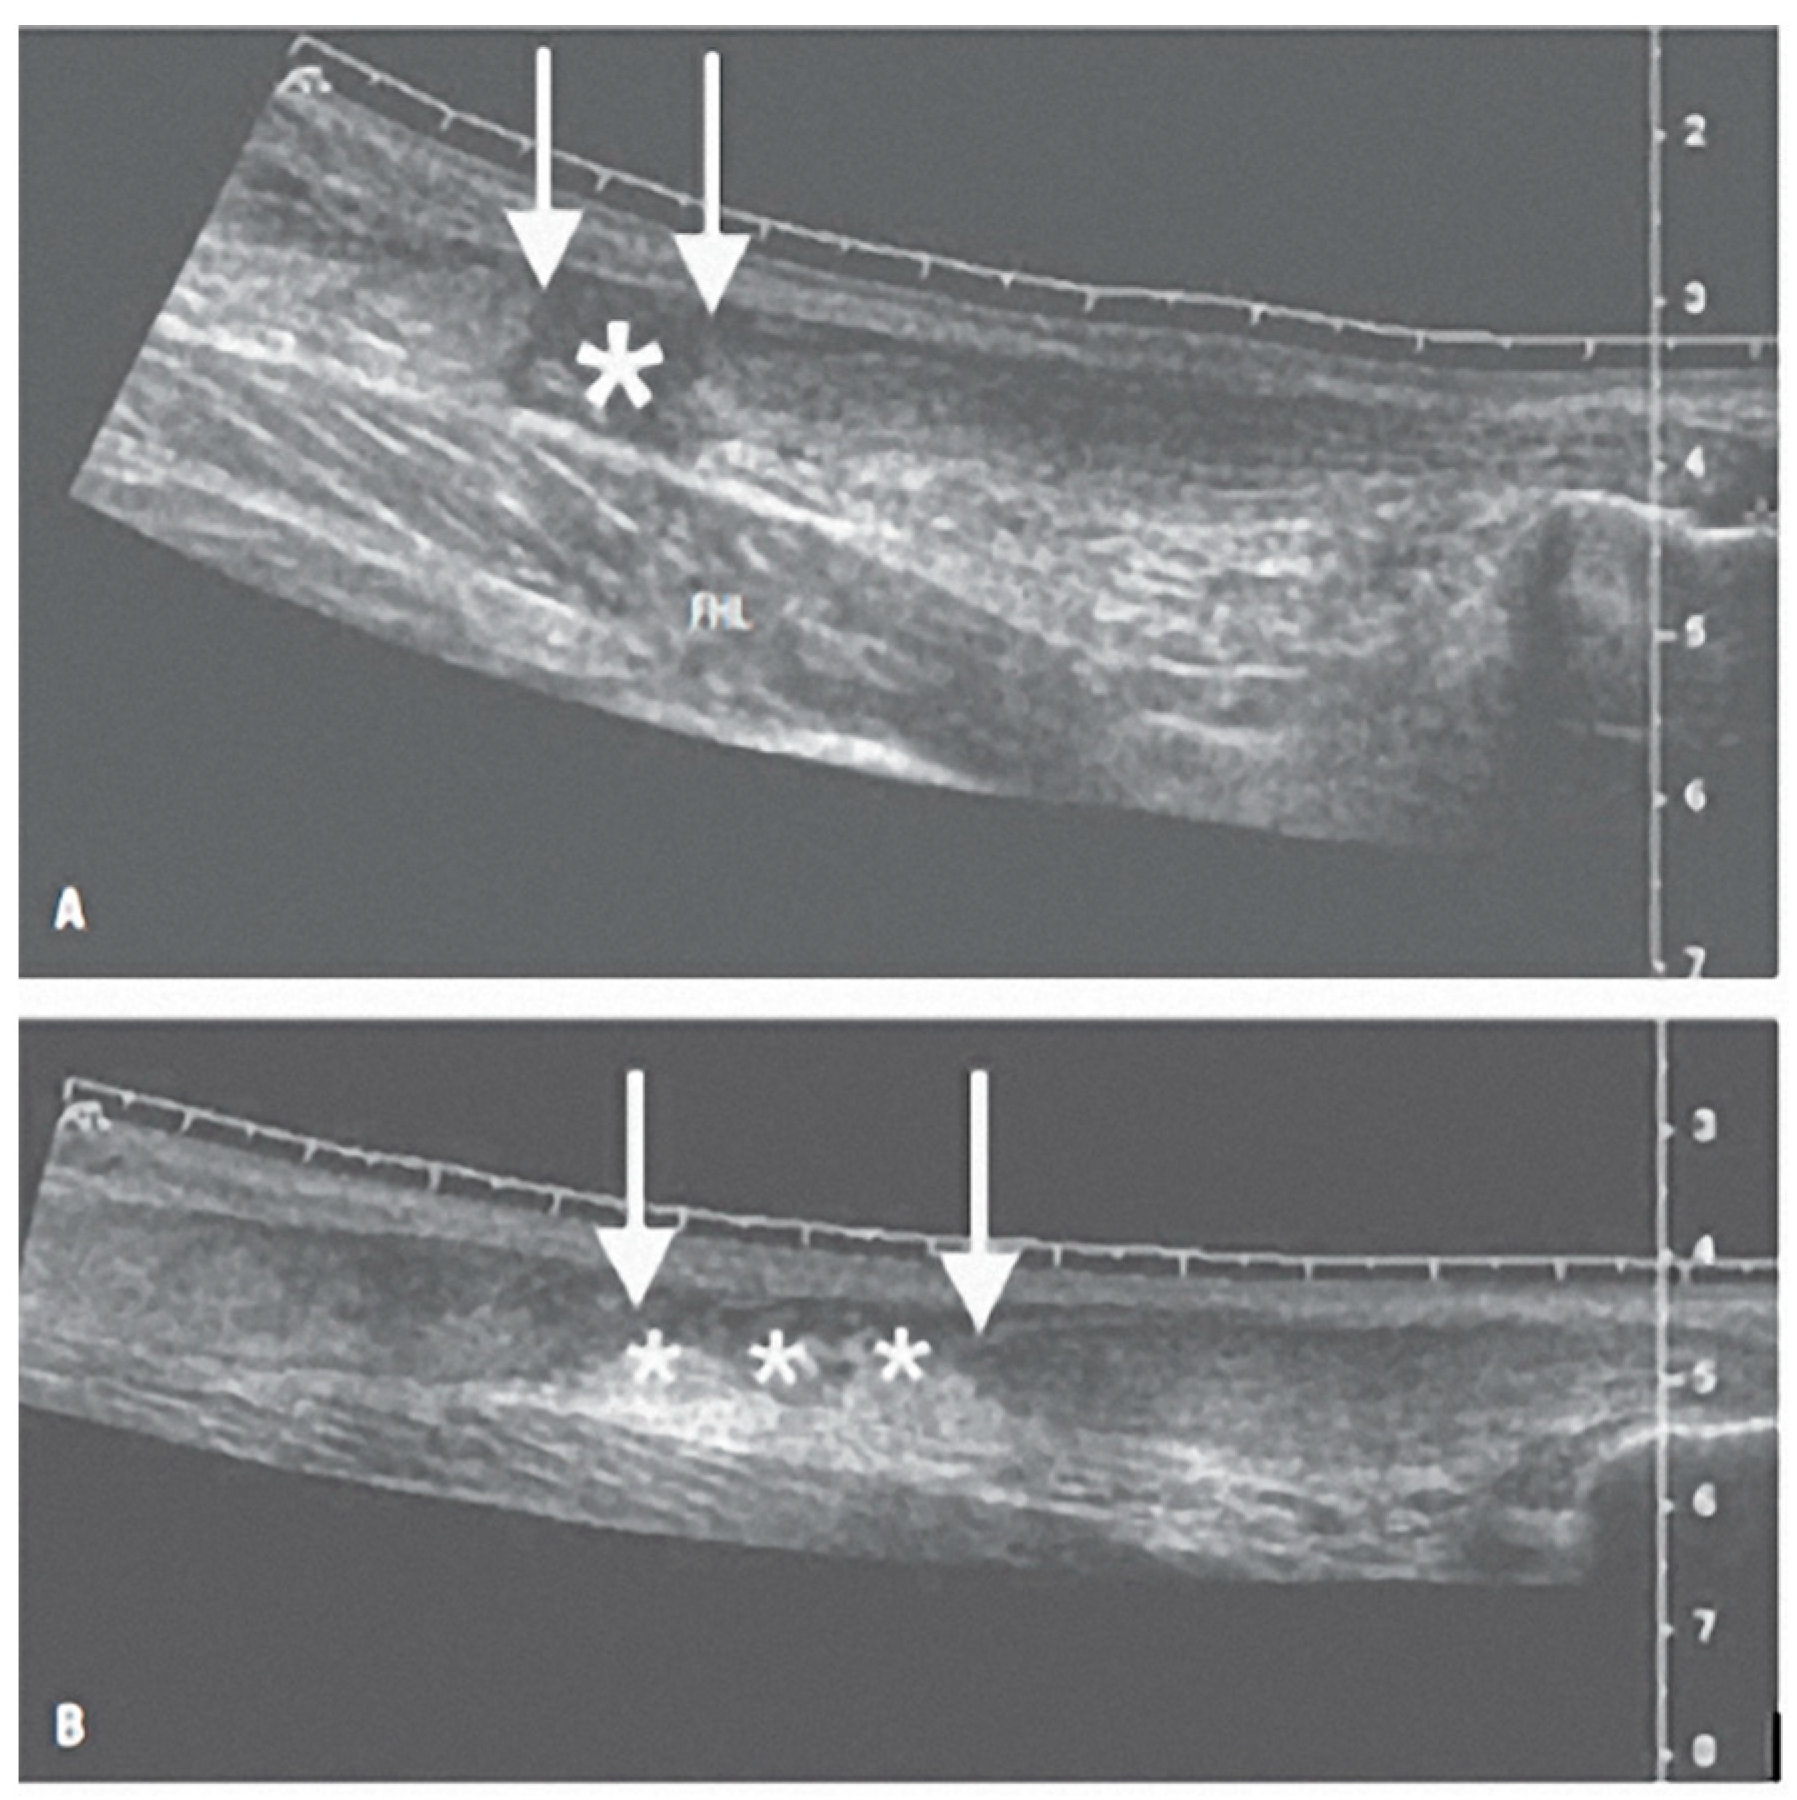

- Gitto, S.; Draghi, A.G.; Bortolotto, C.; Draghi, F. Sonography of the Achilles Tendon After Complete Rupture Repair: What the Radiologist Should Know. J. Ultrasound Med. Off. J. Am. Inst. Ultrasound Med. 2016, 35, 2529–2536. [Google Scholar] [CrossRef] [PubMed]

- Busilacchi, A.; Olivieri, M.; Ulisse, S.; Gesuita, R.; Skrami, E.; Lording, T.; Fusini, F.; Gigante, A. Real-Time Sonoelastography as Novel Follow-up Method in Achilles Tendon Surgery. Knee Surg. Sports Traumatol. Arthrosc. Off. J. ESSKA 2016, 24, 2124–2132. [Google Scholar] [CrossRef]